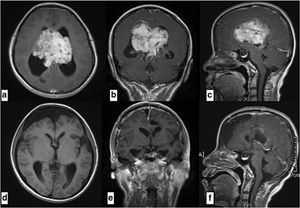

Can you identify this abnormally and treatment?

Chorioidpapilloma, hydrocephaly. Removing of cancer, relising a flow of CSF

Epandimoma and hydrocephaly?

prob. Ependymoma since the affected part lies on the ventricles. And by principle, ventricles are lined with tissues composed of ependymal cells